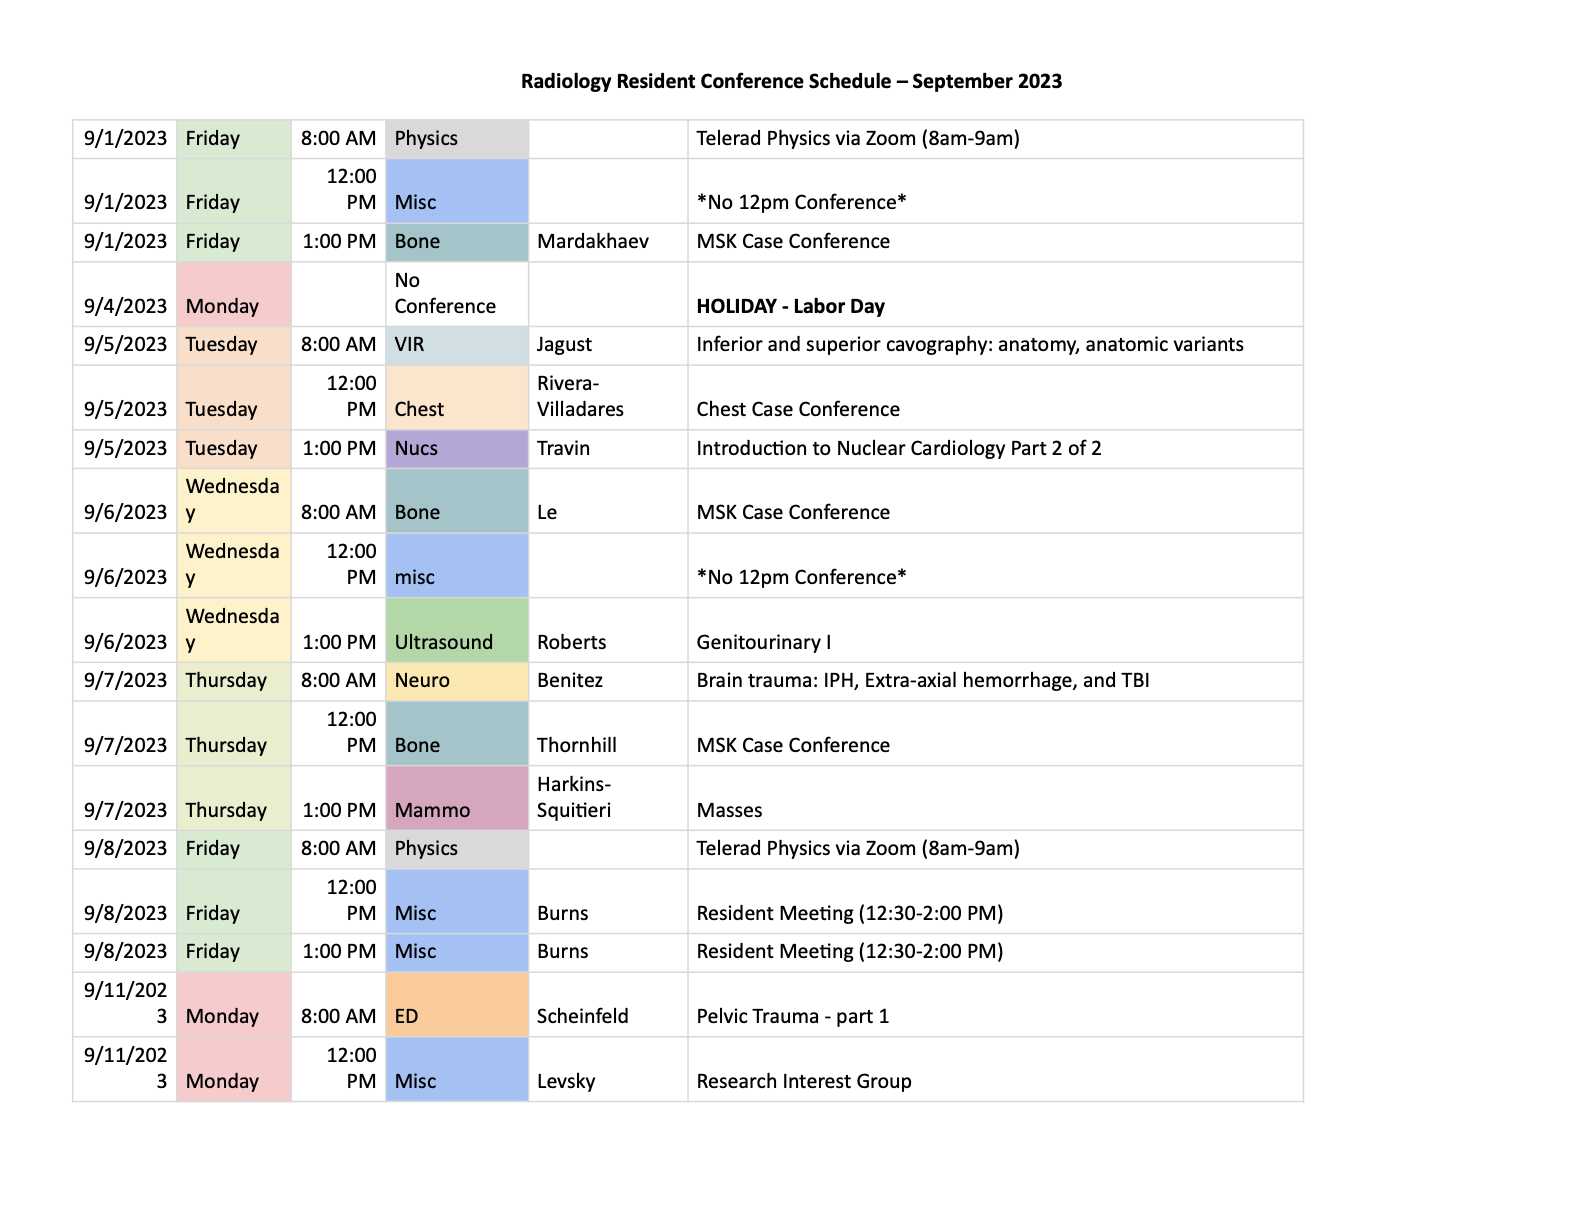

Moses Campus is the primary teaching site for our training programs. Our sub-specialty reading rooms serve as a hub for active clinical care and teaching, and support tertiary-level referral programs throughout the entire breadth of adult and pediatric medicine. In addition to specialized reading rooms, residents have full access to our resident library and a newly renovated resident lounge, and are invited to take advantage of our 3D imaging lab. Resident conferences are presented in-person from Binswanger Auditorium, although we electronically simulcast lectures and conferences from Moses to all our clinical sites. Resident learning is enhanced through participation in a range of interdisciplinary tumor boards and research programs.